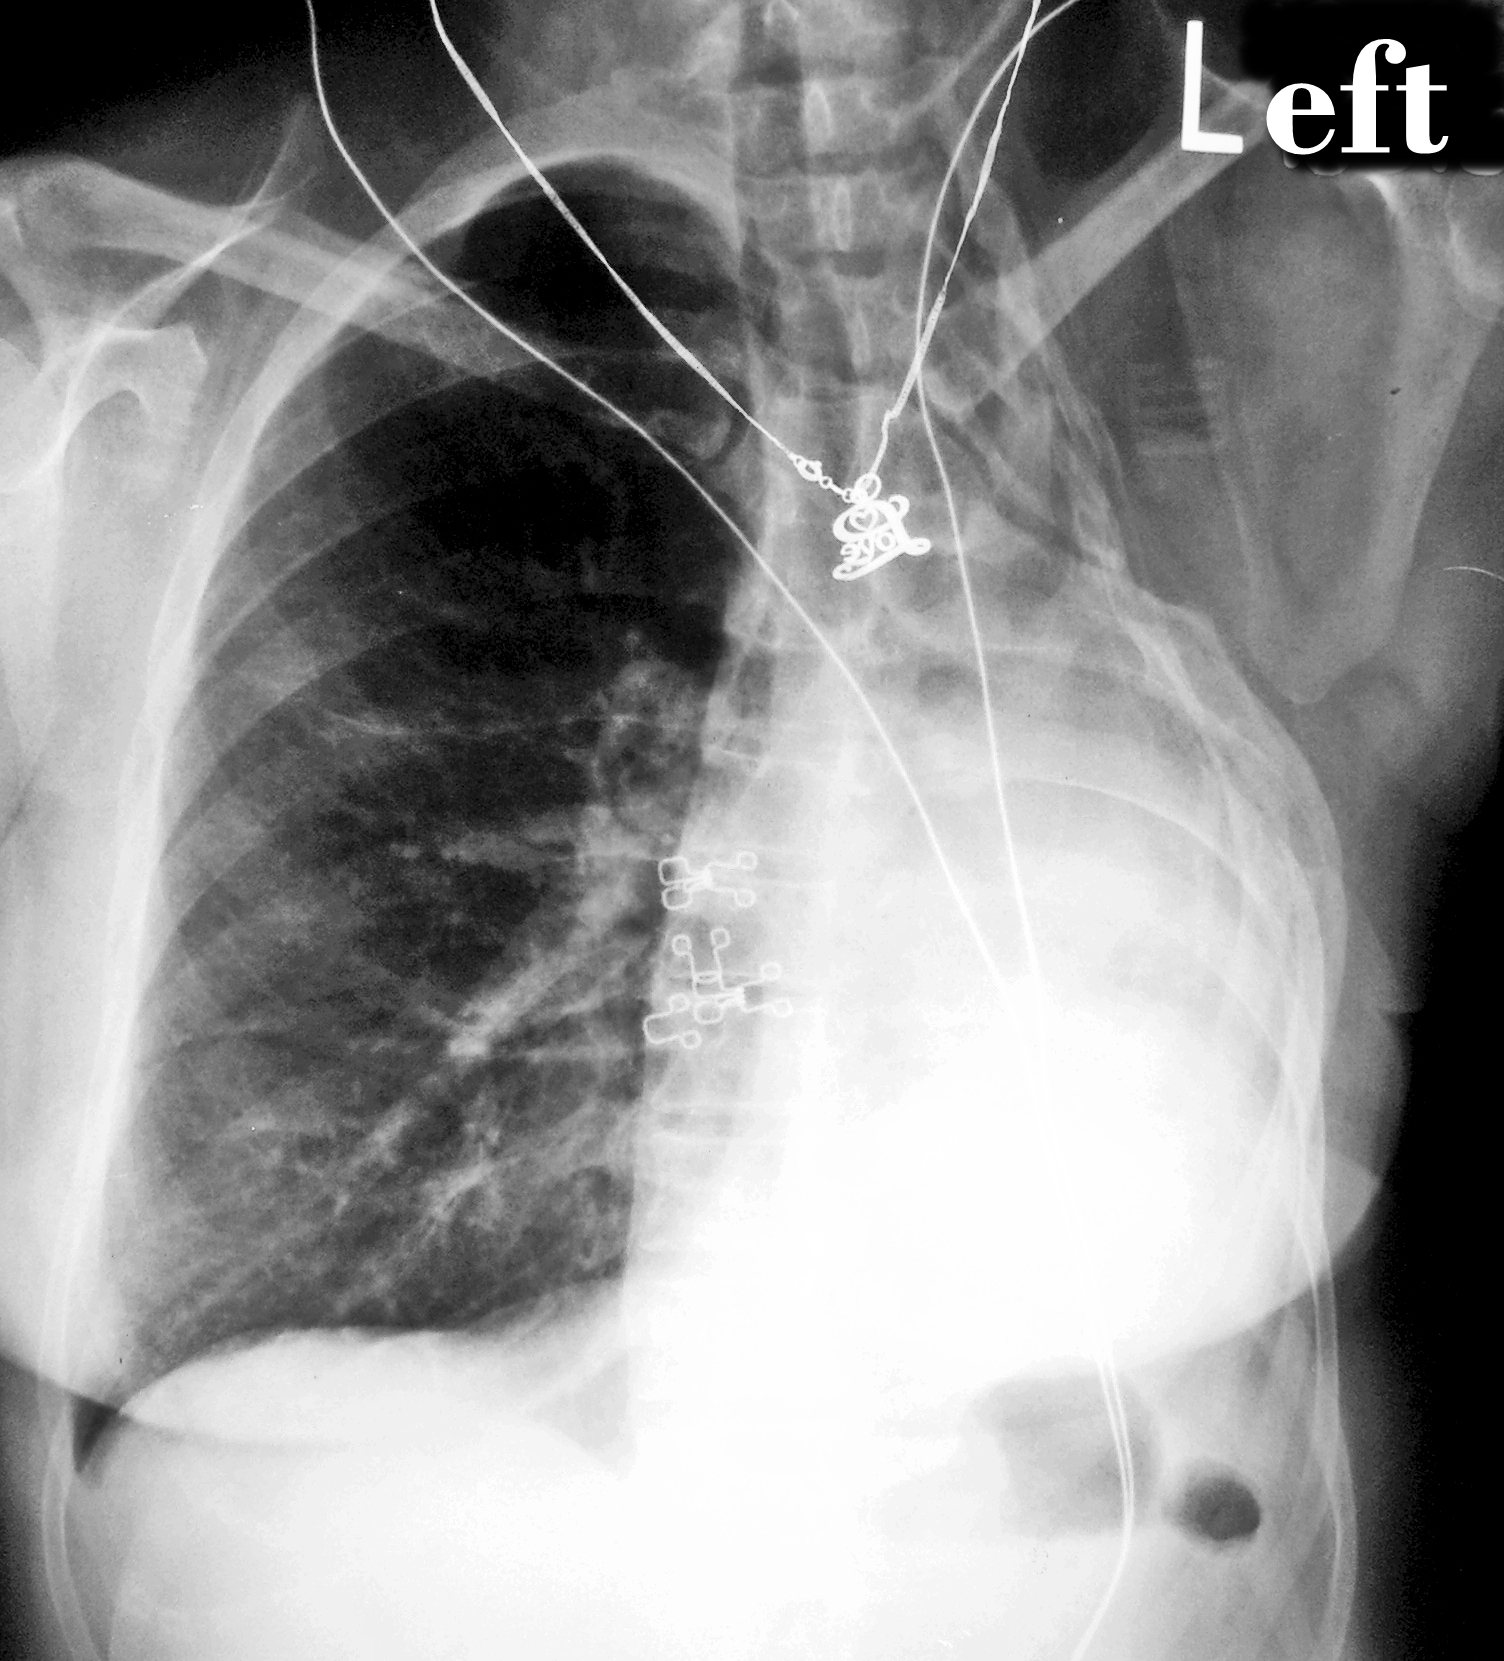

When Katherine first started to feel sick, she thought she had the flu or some other type of respiratory infection. She had a cough, trouble breathing, and chest pains. This is part of what makes mesothelioma so insidious. This is a cancer that attacks the lining of tissue around the lungs. It is most often caused by exposure to asbestos, but it does not develop into symptoms until decades after the exposure occurs.

In the meantime, people like Katherine have no idea that they are getting sick. When they do start to experience symptoms, they are often diagnosed as having an infection, pneumonia, or even lung cancer. Luckily for Katherine, although she was not diagnosed correctly right away, she still received her diagnosis when the cancer was in an early stage. Others are not so lucky and do not get an accurate diagnosis until much later.

Even though Katherine was diagnosed with stage I, or early stage, mesothelioma, her prognosis was still not good. Most people do not survive this cancer, even when treated in the early stages. Her doctors gave her an estimate of about two years if she was lucky. She was only 49 and not willing to accept those odds.

Katherine opted for the most aggressive and riskiest treatment option, but also the one most likely to cure her cancer. As optimistic as ever, Katherine underwent an extrapleural pneumonectomy. Her surgeon removed the tissue called the pleura, in which the cancer originated, her entire right lung, and part of her diaphragm. She followed up this major and risky surgery with months of radiation treatment to try to kill every last cancer cell.